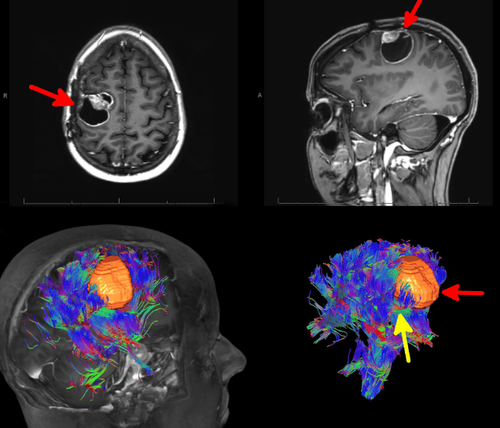

Khả năng phát hiện đường đi của các bó sợi thần kinh trong não sử dụng hình ảnh khuếch tán theo lực được gọi là hình bó sợi thần kinh. Hình bó sợi thần kinh giúp tạo ra các hình ảnh hai hay ba chiều của hệ thống các sợi thần kinh não, từ đó hình ảnh đa chiều hơn giúp bác sĩ có thể dễ dàng đánh giá, phát hiện những bất thường, vị trí tổn thương.

Trong u não, kỹ thuật chụp cộng hưởng từ bó sợi thần kinh cho phép xác định sự xâm lấn hay đè đẩy các bó sợi thần kinh, liên quan u não và các sợi thần kinh các thông tin rất quan trọng trong lập kế hoạch điều trị u não.